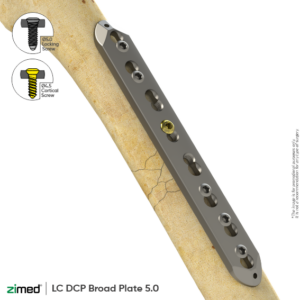

Large Fragment Locking Plate System

Locking LC DCP Narrow Plate (4.5 Mm)